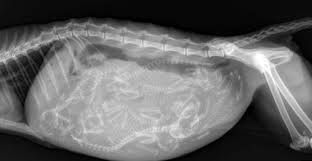

Fanta vemhes!

15 nap múlva meglesznek a kiscicák.